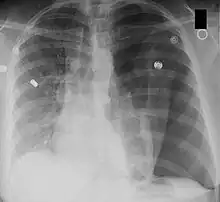

Left-sided tension pneumothorax. Note the area without lung markings which is air in the pleural space. Also note the tracheal and mediastinal shift from the patient's left to right.

A chest X-ray can rapidly identify a pneumothorax, seen as absence of lung markings. Ultrasound can show the lack of lung sliding. However, imaging should not delay treatment.[8] CT angiography is the standard of diagnosis of pulmonary embolism. Clots appear in the vasculature as filling defects.[18]